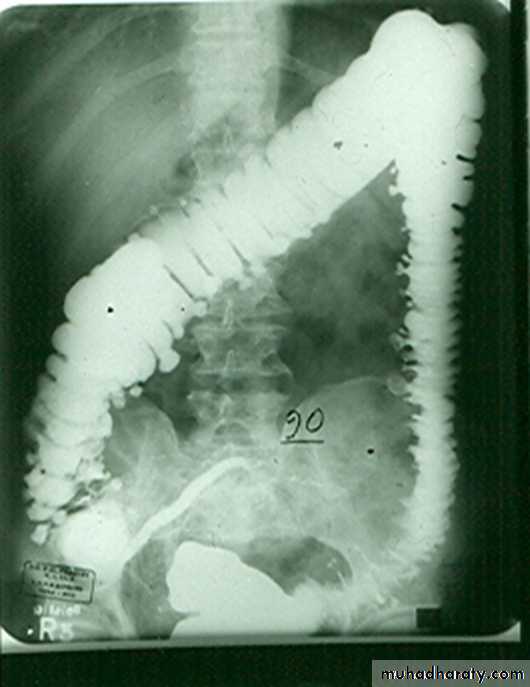

congenital megacolon (Hirschprung disease )

• There is one or more segment of colon devoided from innervation resulting in constriction with proximal dilatation of rest of colon due to weak innervation .• The agangloinic segment usually short , at or near the recto- sigmoid junction .

congenital mega colon

• Rarely the whole colon can be affected result in micro-colon .• 5. Clinically the patient suffering from constipation and abdominal distention since birth .

• 6. The value of Ba Enema is to spot the narrow segment especially prior to surgery .

• 7. Instant Ba Enema is usually done and the Barium used is usually hypertonic .

• Views of particular importance include:

• early filling views that include rectum and sigmoid colon allowing for rectosigmoid ratio to be determined.

• transition zone